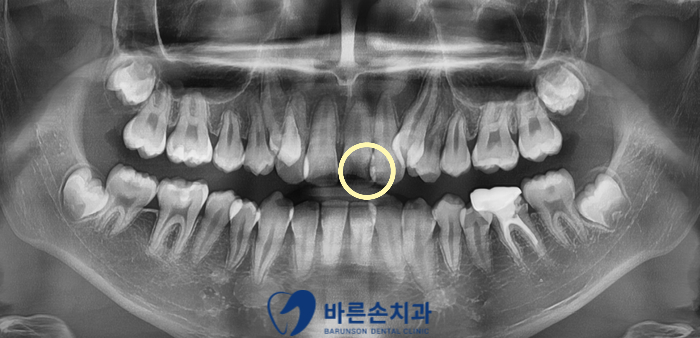

충치의 진행 정도를 보기 위해서 파노라마 사진을 확인해 봤습니다.

파노라마 사진을 보시면 동그라미 부분에

까맣게 충치가 진행되어 있는 모습을 보실 수 있습니다.

치아의 가운데에는 신경이 있는데 충치가 신경 가까이 진행되어 있기 때문에

충치를 제거하면서 신경치료를 진행해야 하는 상황입니다.